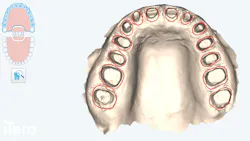

Intraoral digital scans (figure 4) were obtained for comprehensive evaluation of interocclusal relationships. In the sagittal view, the patient exhibits a class I molar relationship on the left and a class II relationship on the right. This asymmetry is clinically significant, as the posteriorly positioned right mandible (class II side) has the potential to negatively influence facial symmetry and esthetics if not addressed in the treatment planning phase. Proper recognition of this discrepancy was essential in guiding the development of a full-face rehabilitative protocol and ensuring both functional stability and esthetic balance in the final smile design.

Transverse evaluation revealed significant occlusal and lingual wear patterns, with malposition of teeth relative to the ideal ovoid arch form. Notably, tooth no. 7 was rotated facially, compromising arch symmetry. The patient was also missing teeth nos. 18 and 28. The absence of no. 18 resulted in hypereruption of no. 15 into an open interocclusal space, while the loss of no. 28 contributed to the upper and lower midlines being noncongruent.

From the anterior perspective, the patient presented with a deep overbite, covering approximately 75% of the mandibular anterior dentition, coupled with insufficient overjet. This functional imbalance exacerbated the patient’s parafunctional bruxism and contributed to generalized incisal and occlusal wear. The maxillary midline was also deviated, failing to harmonize with the patient’s facial esthetics.